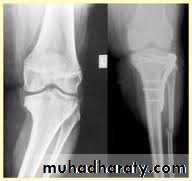

Tibial plateau fractures:

Direct blow or fall from height may cause fracture of one tibial condyle or both.

Fracture lateral condyle is the commonest named as bumper fracture

Patient usually is an adult, the knee joint is swollen, bruises, there is diffuse tenderness and doughy feel of haemarthrosis.

ligaments injuries must be excluded.

Imaging : X-ray

: anteroposterior, lateral & oblique views.

CT -Scan may used to detect amount of depression and comminuation.

Tibial plateau fracture